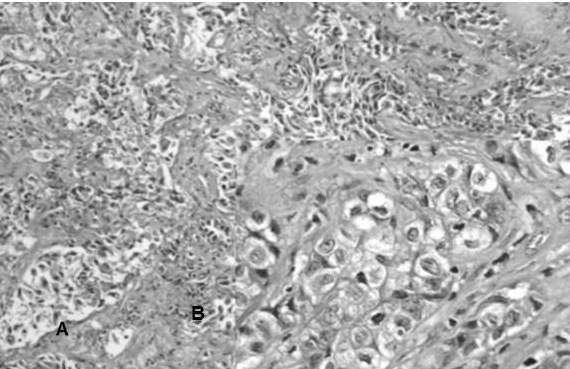

En la reclasificación los casos de ADC estuvieron representados por: ADC patrón predominantemente sólido 57,3 % (Figura 3 y 4), ADC patrón acinar 18,2 % (Figura 5) y en menor frecuencia ADC con patrones mixtos como: patrón predominantemente sólido y acinar 3,6 %, ADC patrón predominante sólido con células en anillo de sello 2,7 %, ADC patrón predominante acinar y micropapilar (Figura 6), patrón predominantemente acinar y sólido, papilar y acinar y patrón predominantemente papilar (Figura 7) cada uno con 1,8 %, asimismo, se encontraron en menor cantidad los siguientes patrones: lepídico no mucinoso (Figura 8) tipo intestinal (Figura 9), mucinoso (Figura 10), y otros patrones mixtos con 0,9 % cada uno (Cuadro 4)

Por otro lado se reclasificaron 50 casos de carcinoma de CCE: encontrando que el CCE poco diferenciado no queratinizante representó el 40 % de los casos (Figura 11), el CCE bien diferenciado queratinizante resultó el 36 % (Figura 12), el CCE moderadamente diferenciado queratinizante representó el 20 % (Figura 13) y finalmente el CCE basaloide (Figura 14) fue el 4 % (Cuadro 7)